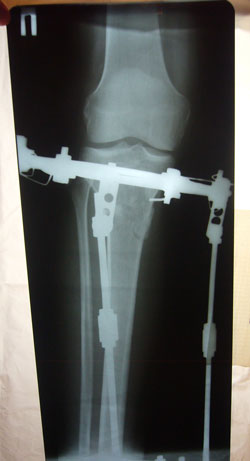

рентгеновские снимки от 03.01.2013г.

2 месяца с момента операции.

P1060108.JPG

P1060107.JPG

P1060106.JPG